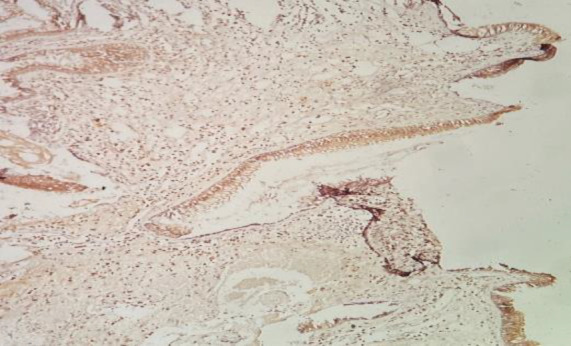

Materials and methods: This prospective study included patients with CAM, CNM, and healthy individuals who underwent surgical management. Immunohistochemistry was performed in the sino-nasal tissue to detect the presence of ACE2 and TMPRSS2 receptors. The level was compared among the three groups.

Results: The study encompassed 44 patients with CAN, 20 with CNM, and ten healthy individuals. ACE2 positivity was seen only in the apical cilia, with no significant difference among the groups (p=0.6). In contrast, TMPRSS2 positivity was seen in the cytoplasm and nucleus of epithelium and submucosal glands in addition to apical cilia. TMPRSS2 was increasingly expressed in patients with CAM compared to CNM (p=0.009) and the healthy group (p=0.002).